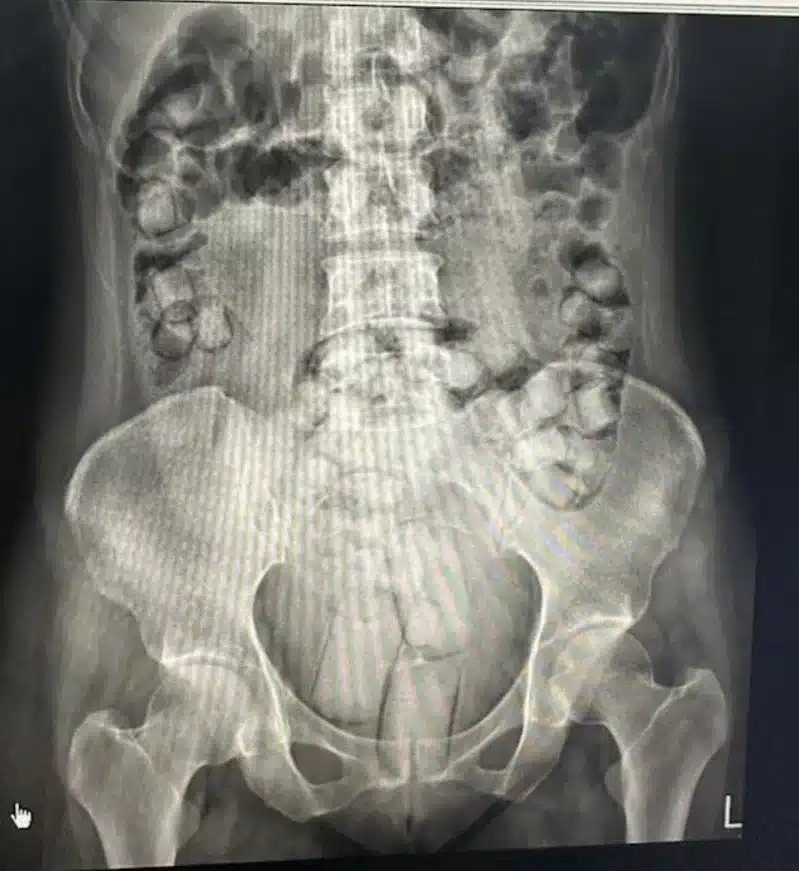

อย่างไรก็ตาม แผนการของทั้งคู่นั้นไม่สำเร็จ เมื่อเดินทางถึงสนามบินนานาชาติเกาสง ของไต้หวัน ในช่วงเย็นวันเดียวกัน เจ้าหน้าที่ชุดปฏิบัติการพิเศษได้ทำการตรวจค้นและจับกุมทันที หลังนำตัวส่งโรงพยาบาลเพื่อเอกซเรย์ พบวัตถุก้อนแข็งจำนวนมากอัดแน่นอยู่ในร่างกาย แพทย์จึงต้องให้ยาถ่ายเพื่อขับออกมา ผลการตรวจสอบยืนยันว่าเป็นเฮโรอีนบริสุทธิ์รวม 115 ก้อน น้ำหนักกว่า 442 กรัม รวมมูลค่าสูงถึง 8 ล้านดอลลาร์ไต้หวัน (ประมาณ 7.9 ล้านบาท)